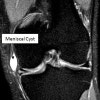

MRI에서 활액과 비슷한 성분으로 내측 반월상 연골판의 내측, 외측 반월상의 외측에 주로 나타납니다.

MRI : 반월상 연골 낭종(Meniscal cyst, Parameniscal cyst)